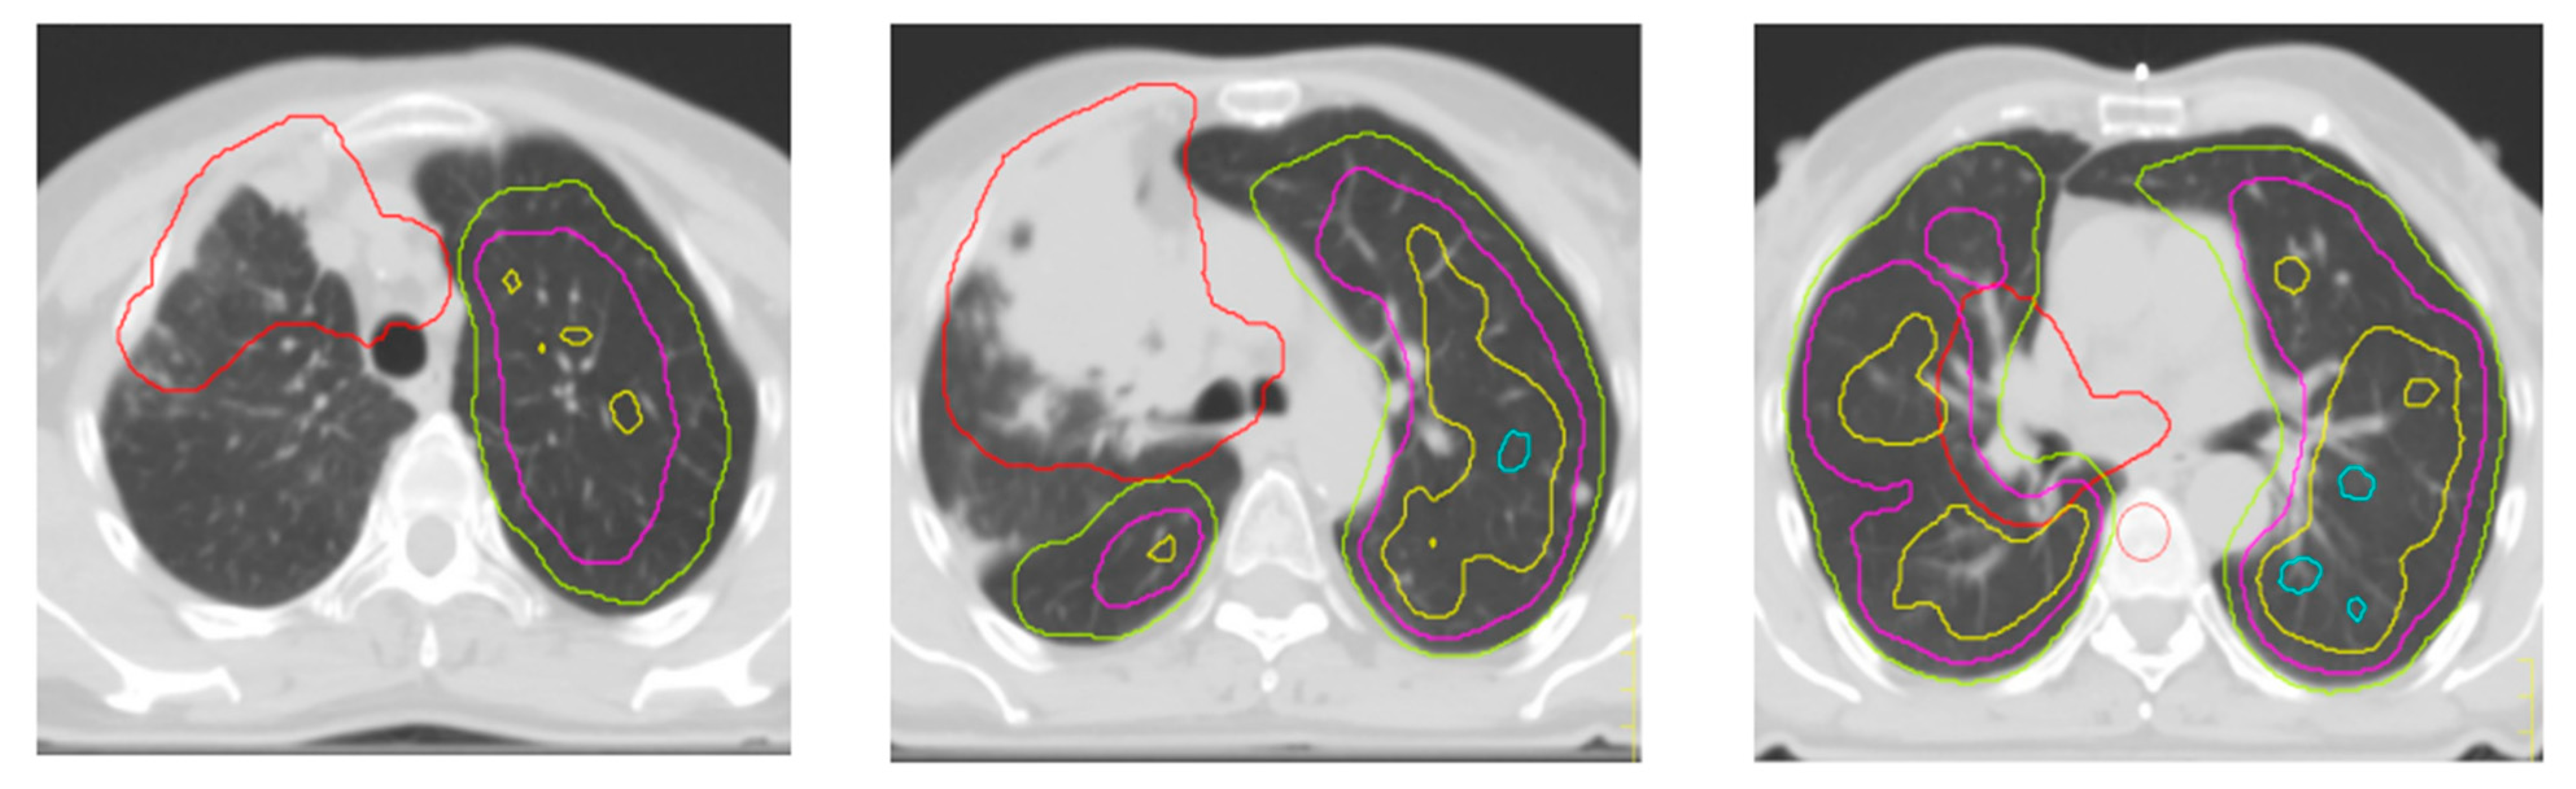

Since the exploratory nature of this study, the regions of interest representing lung volumes with a perfusion of at least 20% 40%, 60% and 80% of the maximum perfusion value were created on the treatment plan (xx%IsoROI) (Figure 2).

Finally, a second plan optimization was developed giving priority to 80% isoROI with the purpose to preserve the most perfused lung areas and to maintain the same OARs doses obtained from the standard plan.

Figure 2. Red: PTV; green: isoROI 20%; magenta: isoROI 40%; yellow: isoROI 60%; light-blue: isoROI 80%.